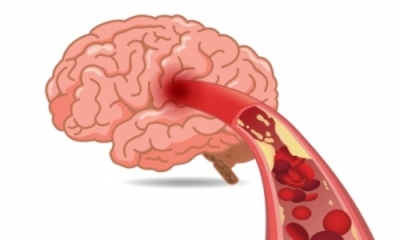

우리나라에서 단일 질환으로 사망률 1위는 뇌졸중이라고 하는데요. 뇌졸중은 뇌의 혈관이 좁아지면서 혈관이 막히며 발생하는 질환입니다.

고혈압이나 당뇨 같은 위험인자를 지닌 사람은 더욱 위험하며 술, 담배, 짠 음식, 기름진 음식 등 혈관 건강을 망치는 음식이나 습관들도 뇌졸중 위험을 높이는 인자 중에 하나입니다.